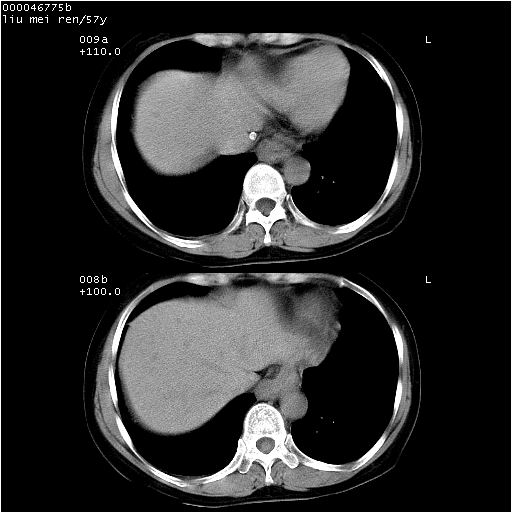

患者 女,57岁。因车祸受伤,其家属要求行“全身ct检查”。平素健康。

胸部ct轴位平扫(层厚10mm,螺距1.5,重建间隔10mm),图像如下:

上腔静脉变异

左位上腔静脉,先天变异。